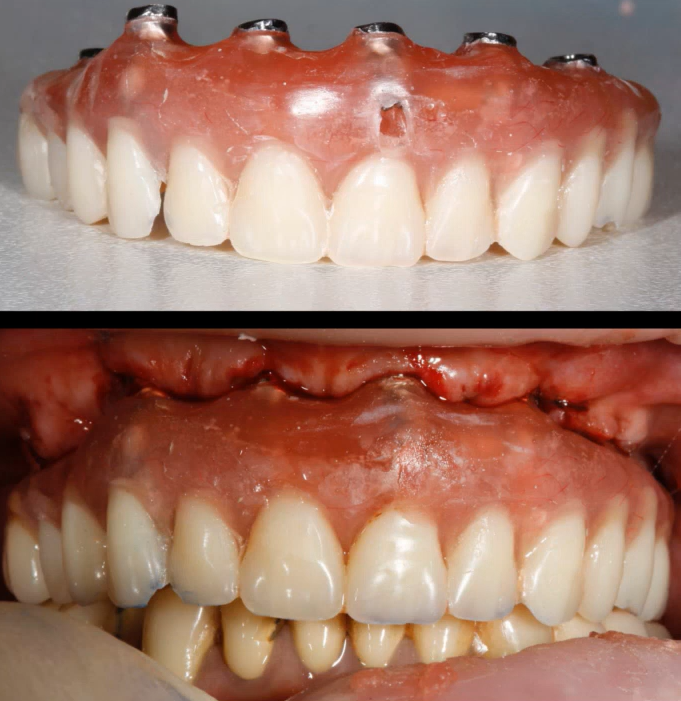

Examples of successful immediate implant placements followed by prosthetic restoration are shown in the images below. As can be seen, the angled implants also integrated well and the restoration is sound.

An example of restoration on implants placed immediately after tooth extraction. YouTube/ Dr. Sergey Rozhnov /sergiodontolog

While contraindications to immediate implantation exist, they are relatively rare. Angled implant placement also deserves special attention. Although the load is distributed unevenly and the abutment and retention screw experience greater stress compared to axial placement, an angled implant allows the clinician to: